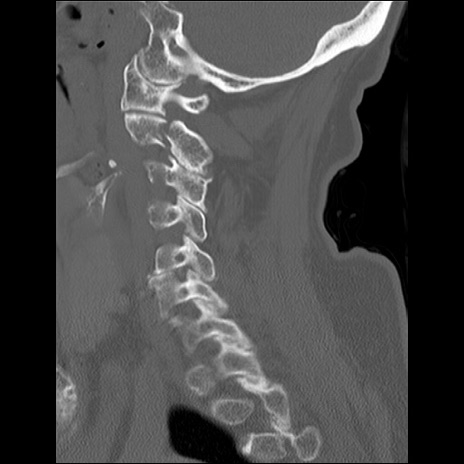

症例48 頚椎CT(矢状断像)

頚椎CT